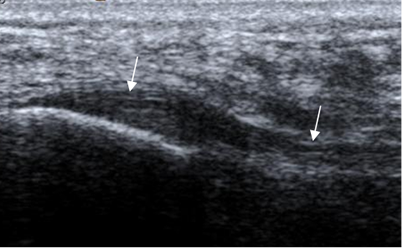

En ecografía, los ligamentos son estructuras lineales e hipoecoicas, con un espesor menor a 2 mm. (4). (Fig 9 y 15).

Fig 9. Ligamentos peroneoastragalinos normales en ecografía.

Ligamento peroneoastragalino anterior en A y peroneoastragalino posterior en B.